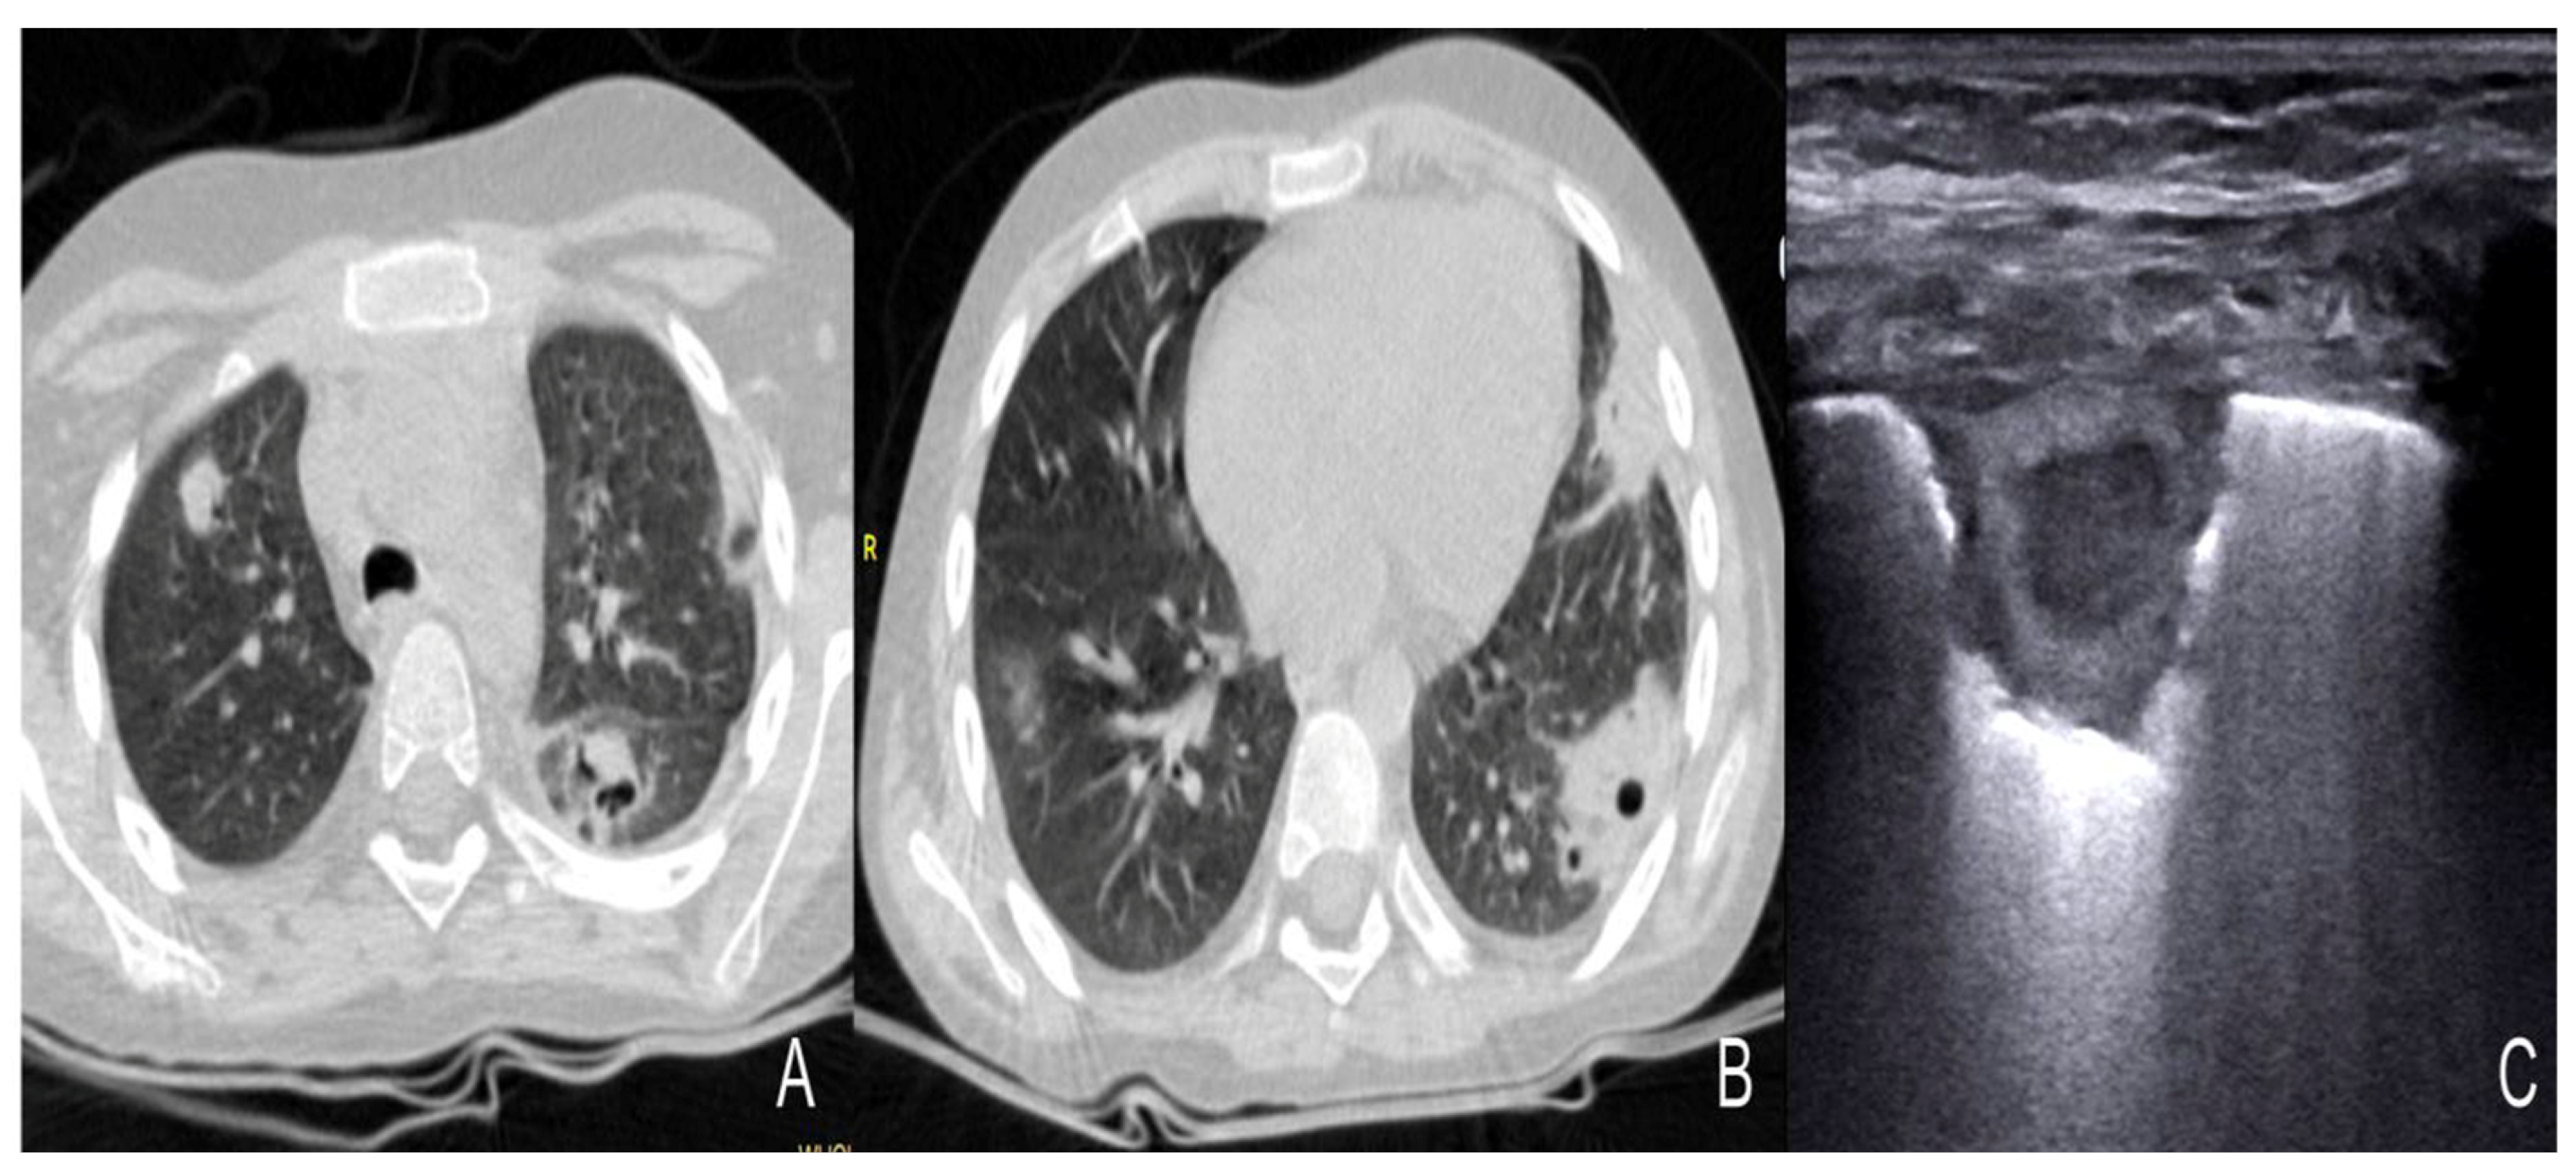

- Li, S.; Zhang, Q.L.; Guo, R.J.; Lv, X.Z.; Yang, X. Quantitative evaluation and significance of ultrasound in bronchoalveolar lavage for lung consolidation in children with severe mycoplasma pneumonia. Transl. Pediatr. 2021, 10, 2325–2334. [Google Scholar] [CrossRef]

- Tripaldi, C.; Polito, M.; Iacoviello, O.; Basile, V.; De Bellis, T.; Fortunato, M.; Laforgia, F.; Scalini, E.; Silletti, M.; Lofù, I. Ultrasound Studies on Mycoplasma Bronchopneumonia. J. Curr. Med. Res. Opin. 2021, 5, 1301–1315. [Google Scholar] [CrossRef]

- Buonsenso, D.; Musolino, A.; Ferro, V.; De Rose, C.; Morello, R.; Ventola, C.; Liotti, F.M.; De Sanctis, R.; Chiaretti, A.; Biasucci, D.G.; et al. Role of lung ultrasound for the etiological diagnosis of acute lower respiratory tract infection (ALRTI) in children: A prospective study. J. Ultrasound 2022, 25, 185–197. [Google Scholar] [CrossRef]

- Liu, G.; Wang, G.; Yang, Z.; Liu, G.; Ma, H.; Lv, Y.; Ma, F.; Zhu, W. A Lung Ultrasound-Based Nomogram for the Prediction of Refractory Mycoplasma pneumoniae Pneumonia in Hospitalized Children. Infect. Drug. Resist. 2022, 31, 6343–6355. [Google Scholar] [CrossRef]